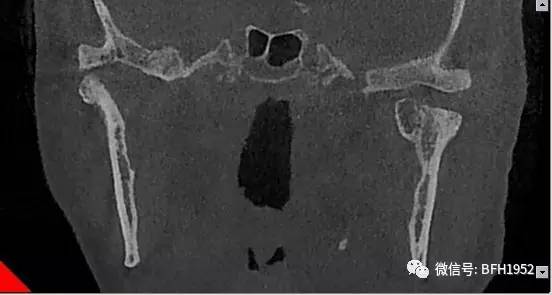

2月16日,经过充分完善的术前准备,口腔科为患者实施了手术。术中患者被动开口度达到43mm,术后咬合关系基本正常,面部左右对称。术后2周复查,患者主动开口度达到23mm,咬合关系及进食功能得到明显改善。

术后

术后两周